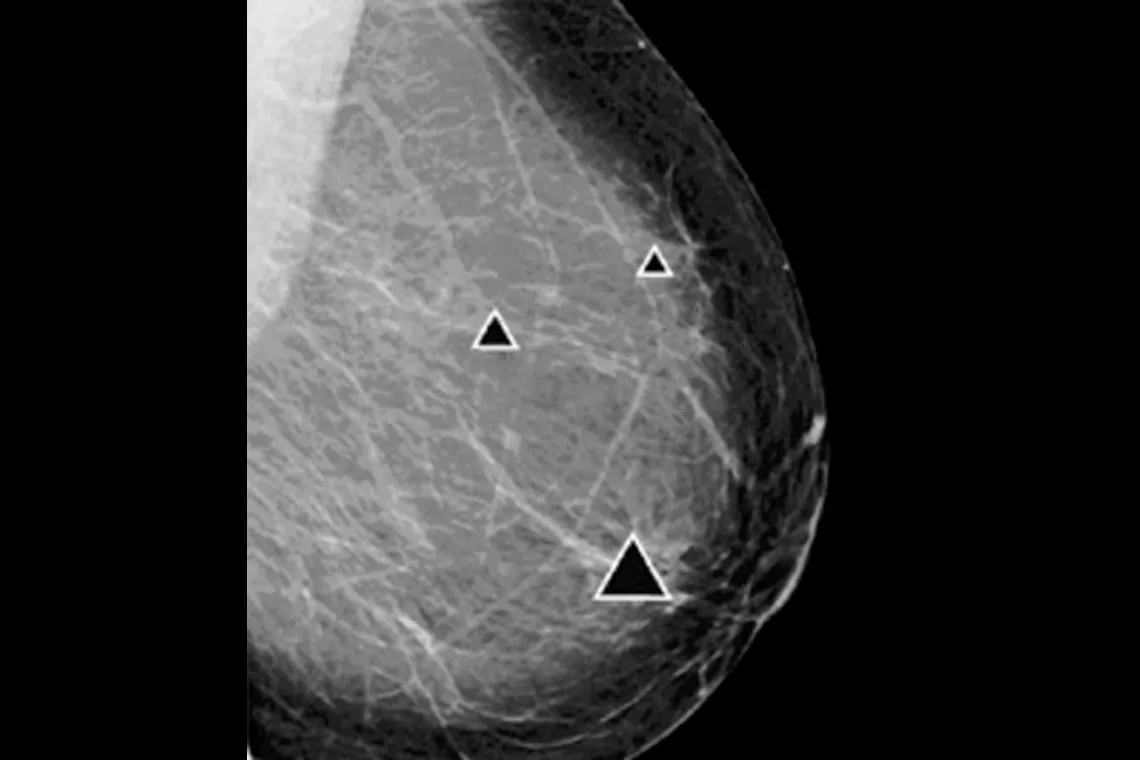

ImageChecker 2D CAD Technology searches digital mammograms for potential microcalcifications and masses, characteristics commonly associated with breast cancer.

- Regions-of-interest are highlighted for the radiologist’s attention

Image Gallery3